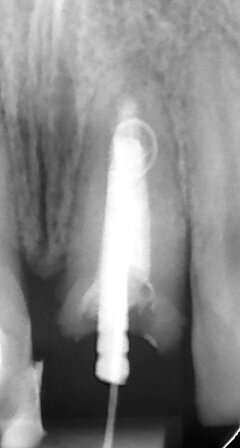

MTA è il materiale che vanta i migliori risultati come materiale da otturazione per la chirurgia apicale. L’MTA è stato associato ad una minore infiammazione, a formazione di nuovo cemento e alla rigenerazione del tessuto periradicolare (Torabinejad e Chivian 1999) (Figg. 4a-4f).

Chirurgia apicale